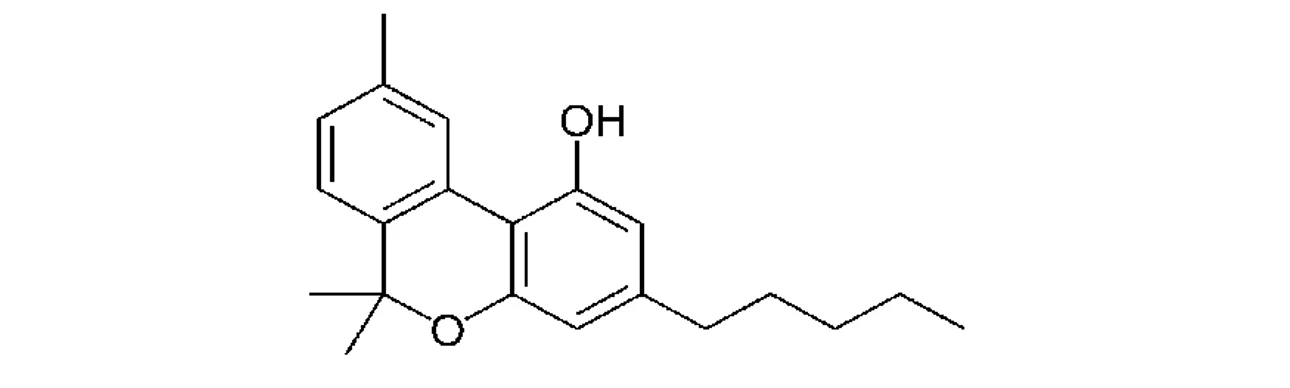

PČR: Kanabinol (CBN) – jeho koncentrace roste během skladování, zatímco koncentrace THC klesá, vzniká při rozkladu dalších kanabinoidů (10)

PČR: Kanabinol (CBN) – jeho koncentrace roste během skladování, zatímco koncentrace THC klesá, vzniká při rozkladu dalších kanabinoidů (10)